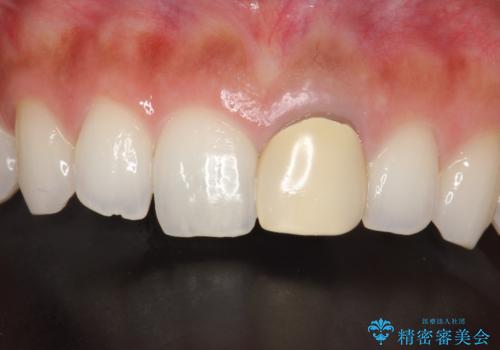

前歯のかぶせ物の色があっていない オールセラミック治療

- 以前装着された前歯のかぶせ物の色を変えたいとのことで来院されました。

土台からの再治療を行い、オールセラミッククラウンを装着する治療計画としました。

保険適用のかぶせ物は天然の歯のような色見を表現するのは難しいといえます。

自然な歯をご希望な場合、金属を使わないオールセラミックがおすすめです。